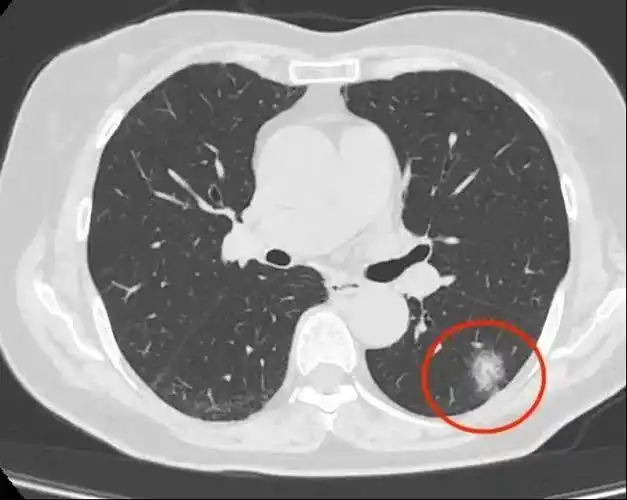

体检疑似肺癌?别急,ct引导下肺穿刺活检术为您明确诊断!